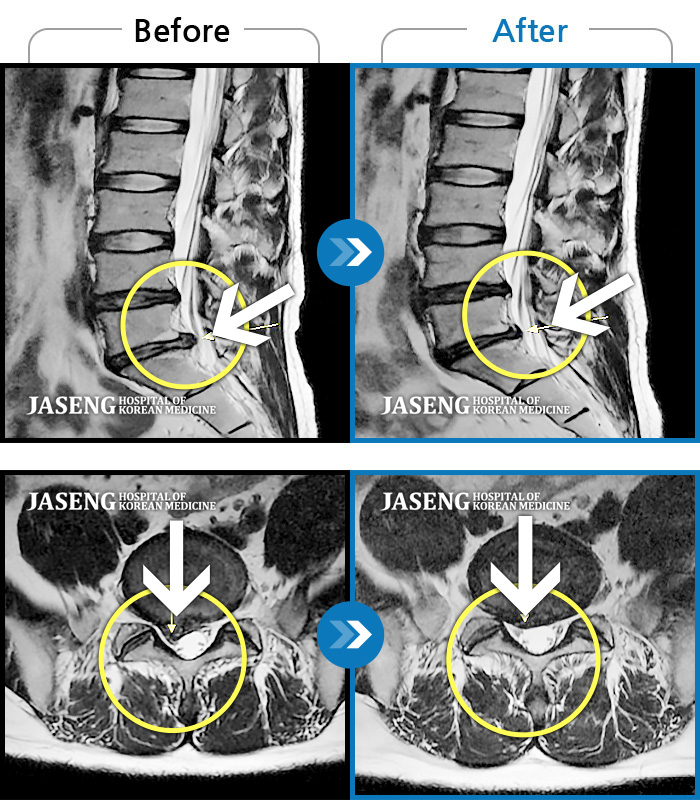

Before

After

환자에게 사전 동의를 받아 동일 조건에서 촬영되었습니다.

개인에 따라 치료 후 부작용이 발생할 수 있으니 의료진과 상담 후 치료를 진행하시기 바랍니다.

허리 및 우측 하지 통증

허리디스크로 인한 골반 통증